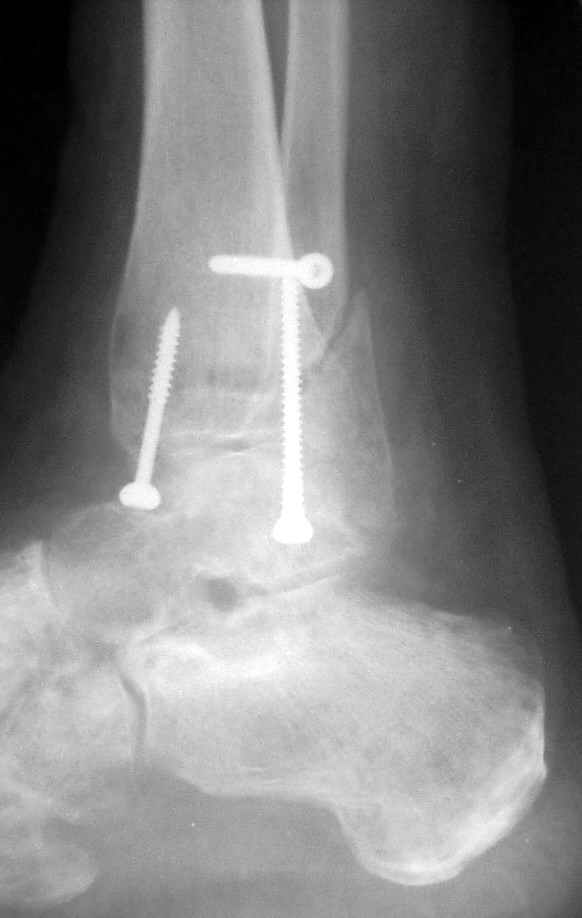

Через месяц

Боковой через месяц